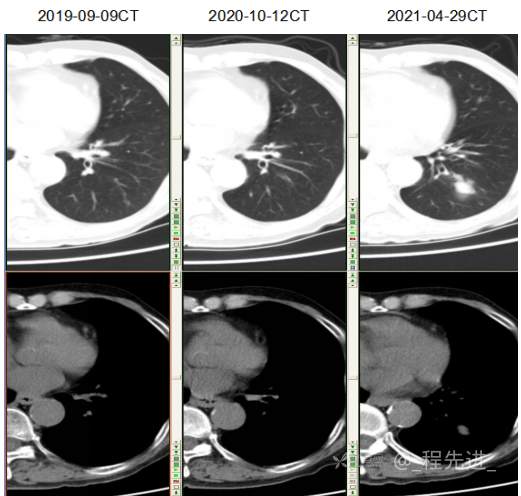

主诉: 反复咳嗽、咳痰10余年,加重10余天

现病史:患者10年前开始出现反复咳嗽、咳痰,3年前出现活动性气喘,休息后症状可缓解;冬春季节或受凉后症状加重,不伴反复下肢浮肿,曾在我院住院诊断为”慢性阻塞性肺疾病”,给予解痉平喘、化痰、输氧治疗有效,平素生活能自理,不能从事体力劳作,此次发病于10天前可能受凉后咳嗽、咳痰加重,咳黄痰,呈阵咳,咳白痰,活动气喘加重,不伴畏寒、发热,无胸痛,今来我院就诊,拟“慢性阻塞性肺病伴急性加重”收住入院,自发病以来,患者精神、食纳、睡眠一般,大小便如常,体重有下降,县体不详。患者及陪护人员:否认14天内离开过南丰,否认14天内有新型冠状病毒感染病例报告社区或中高风险地区的旅行史或居住史,否认14天内与新型冠状病毒感染的患者或无症状感染者有接触史,否认14天内曾接触过来自有病例报告社区或中高风险地区的发热或有呼吸道症状的患者,否认14天内在小范围如家庭、办公室、学校班级等场所,出现5例及以上发热和/或呼吸道症状的聚集性发病病例。

既往史:平素健康状况 一般,有胃大部分切除病史40年,去年10月复查胃镜提示吻合口溃疡;肠镜检查多发性结肠息肉。因胸闷、气促去年在心血管科住院,行冠脉造影检查,提示有冠状动脉粥样硬化,但未行支架植入。有前列腺增生病史数年,目前一直口服非那雄胺、盐酸坦索罗辛治疗,有痛风病史数年,未正规治疗,近1年来出现记忆力明显下降、下肢无力症状。否认病毒性肝炎、肺结核、伤寒、疟疾病史否认高血压、糖尿病、高血脂病史 ,否认脑血管疾病史无 静脉血栓栓塞个人史, 否认外伤、中毒, 有胃大切手术史,有腰椎压缩性骨折行手术治疗 , 否认输血史,无药物过敏史,无食物过敏史,预防接种史 不详。